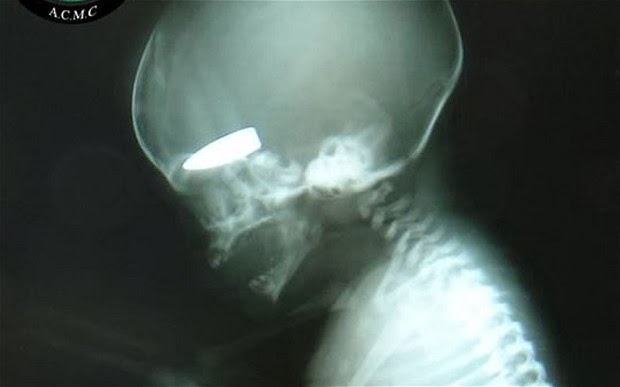

Η βρετανική εφημερίδα δημοσιεύει τη φωτογραφία της ακτινογραφίας που δείχνει ένα έμβρυο να έχει σφηνωμένο στο κρανίο του μια σφαίρα.

Έγκυες γυναίκες είναι στόχοι ελεύθερων σκοπευτών στη Συρία και μάλιστα “επιβραβεύονται” μ΄ αυτό με μερικά πακέτα τσιγάρα. Η αποκάλυψη που δημοσιεύεται στην βρετανική εφημερίδα Telegraph, είναι ανατριχιαστική και συνοδεύεται από τη φωτογραφία ενός εμβρυου στο οποίο έχει “καρφωθεί” η σφαίρα ενός ελεύθερου σκοπευτή. Το ρεπορτάζ της εφημερίδας υποστηρίζει ότι αυτές τις βολές τις κάνουν ελεύθεροι σκοπευτές του Άσαντ οι οποίοι έχουν λάβει σχετικές εντολές να “προτιμούν” ως στόχους τις έγκυες γυναίκες. Και για κάθε τέτοιο στόχο αμείβονται με μερικά πακέτα τσιγάρα!

Σε μία μόνο ημέρα περισσότερες από έξι έγκυες γυναίκες είχαν χτυπηθεί από πυρά ελεύθερων σκοπευτών. Οι περισσότερες επιβίωσαν όχι όμως και τα έμβρυα.